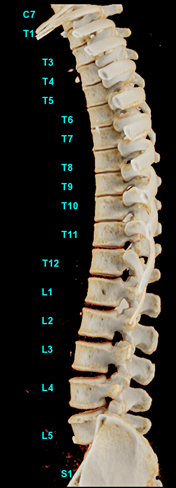

Derin öğrenme sayesinde, bu gelişmiş görüntüleme yazılımı çok geniş bir veritabanı üzerinde belli bir algoritma kullanabilir ve ne kadar çok kompleksite olursa olsun, omurgayı %95 ihtimalle boyundan en uca kadar doğru bir şekilde görüntüleyebilir.

Adeline Digard, hastanelerin gittikçe daha yaygın bir şekilde tanı ve tedavi süreçlerine entegre etmekte oldukları ileri teknolojiler hakkında bazı bilgilere sahip. Kendisi, ayrıca bu teknolojilerin yaratılmasında katkısı bulunan kişilerden de biri. Digard GE Sağlık‘ın Fransa Buc’taki Dijital Ürün yönetimi direktörlüğü görevini yürütüyor. Bu görev kapsamında o ve ekibi çalışma saatlerini katmanlı imalat, sanal gerçeklik ve yapay zekâ gibi uygulamaların sağlık hizmetlerindeki rolünü araştırarak geçiriyor. Yakın bir tarihte, Digard üzerinde çalıştığı ürünlerin önemini açıklamak üzere GE Reports ile bir röportaj gerçekleştirdi. Örneklerden faydalanarak, yapay zekânın omurilik sağlığı üzerinde çalışan doktorlara nasıl yardımcı olabileceğinden bahsetti: Bu bağlamda algoritma öncelikle manifold görüntüleri elden geçirerek omurganın doğru konfigürasyonunu öğreniyor ve “normal” ifadesinin ne anlama geldiğini anlıyor. Ardından omurga anatomilerini ve anomalileri içeren kapsamlı bir veritabanına erişim elde edene kadar skolyoz gibi patolojilere ve pek çok farklı vakaya maruz bırakılıyor.

Bir radyologun BT taramasını okumasına yardımcı olan yapay zekâ müthiş bir kaynak olabilir. Digard, “Halihazırda omurganın tüm oryantasyonlarını hekimden çok daha hızlı bir şekilde gözden geçirmiş ve her bir permütasyonu dikkate almış olan makine, hekimi tespit ettiği her türlü anomaliye karşı uyarıyor” diyor ve ekliyor: “Yazılımın bu evrensel unsurlarla ilgilenmesi, radyologa inanılmaz bir zaman tasarrufu sağlıyor. Yapay zekânın amacı aslında tam da bu… Hekimlerin tüm dikkatini, hastaları için kritik konular üzerinde yoğunlaştırmasını ve zahmetli işlere vakit harcamamasını sağlamak.”